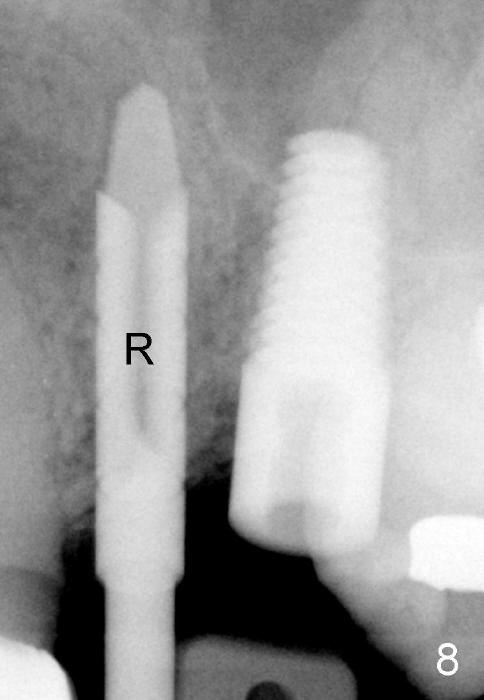

The anterior retainer is kept as a crown at #11 (Fig.2: C), whereas the residual root at the site of #13 is extracted with apical perforation (Fig.3 ^). It is confirmed by Fig.4 (<). To close the perforation, an osteotomy is initiated on the palatal wall of the socket with a 2 mm osteotome (Fig.5 insert: circle). As the osteotomy is being enlarged by a 3 mm osteotome, the bone between the original socket and the osteotomy is being pushed buccally. The former is being closed (Fig.5). The osteotomy is finished with combination of osteotomes and reamers. Fig.6 shows that a 5x14 mm tap is inserted at the site of #13 and that the sinus floor is lifted. In fact the sinus membrane is partially torn at the osteotomy, which is repaired by insertion of Colla-form Dressing (Impladent), followed by autogenous bone (harvested from reamers) mixed with Osteogen (Impladent). A 5x14 mm implant is placed at the site of #13 with insertion torque more than 60 Ncm (Fig.7: I). An incision is made at the site of #12 to start osteotomy with insertion of a parallel pin (Fig.7 P). A 3 mm reamer is kept in place for position confirmation (Fig.8 R). Due to ridge atrophy (Fig.2 arrowheads), a much smaller, but longer implant is placed at the site of #12 (Fig.9: 4x17 mm). The autogenous bone harvested from #12 osteotomy is placed in the buccal gap of #13, followed by insertion of Colla-form Dressing (Fig.10 M). To protect the membrane, a short abutment (4x3 mm) is temporarily placed (Fig.9,10 A) and perio dressing (Fig.9 D) is applied around the abutment and the interproximal areas of the neighboring teeth. Usually perio dressing dislodges around 1 week postop, particularly for a large edentulous space. In this case, the dressing is quite stable 11 days postop: the abutment (Fig.11 A) appears to contribute to retention of the dressing (D).